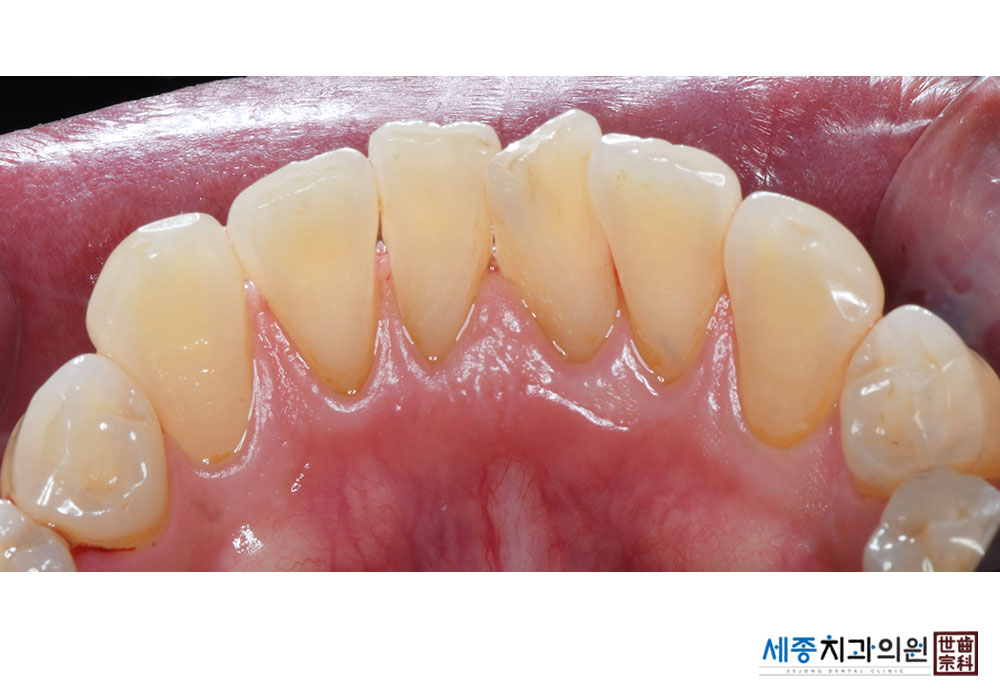

[스케일링] 치주질환 예방 스케일링

치료전 : 2023-12-15

치료후 : 2023-12-15

가글마취&저주파 스켈러를 사용한 착색제거 스케일링